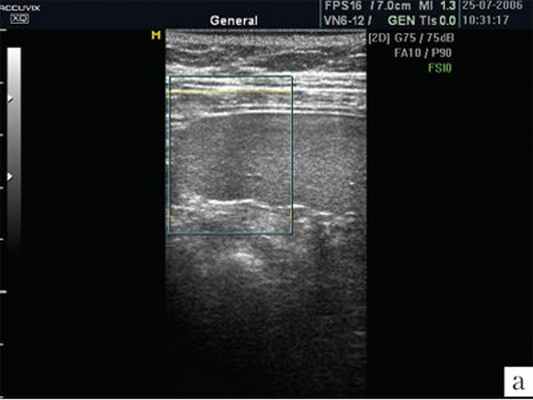

Капсула селезенки чрезвычайно тонкая, поэтому не визуализируется. Но благодаря капсуле изображение края селезенки предстает очень четким, хотя бывает сложно, особенно у полных пациентов, отграничить латеральный край селезенки от брюшной стенки. От капсулы селезенки в паренхиму отходят тончайшие соединительнотканные прослойки, которые намечают деление на дольки, хотя полностью дольчатого строения нет, поэтому орган очень хрупкий, особенно при спленомегалии, когда соотношение паренхимы и соединительной ткани резко изменяется в пользу первой составляющей. В норме эхографическое изображение селезенки гомогенное. Эхогенность селезенки у новорожденных, детей раннего и младшего возраста ниже, чем у взрослых, что объясняется слабым развитием трабекулярной ткани и полностью повторяет возрастную динамику эхоструктуры лимфатических узлов. Эхогенность ворот селезенки выше, чем ее паренхимы. В самой селезенке при использовании датчиков с частотой излучения 3-5 МГц регистрируется большое количество мелких линейных или точечных сигналов. Использование датчиков высокой частоты (13 МГц) позволило доказать, что эти сигналы являются отражением ультразвука от лимфоидных фолликулов (белой пульпы). Коэффициент корреляции с гистологическими находками оказывается очень высоким (r=0,71; p=0,03) [4]. Построение изображения в различных режимах открывает новые перспективы в возможностях оценки структуры селезенки. Ультразвуковое изображение селезенки в режиме МРТ позволяет лучше визуализировать паренхиму, убрать посторонние сигналы (рис. 1).

а) Изображение селезенки при ультразвуковом сканировании в обычном режиме. В паренхиме определяется множество дополнительных эхосигналов.